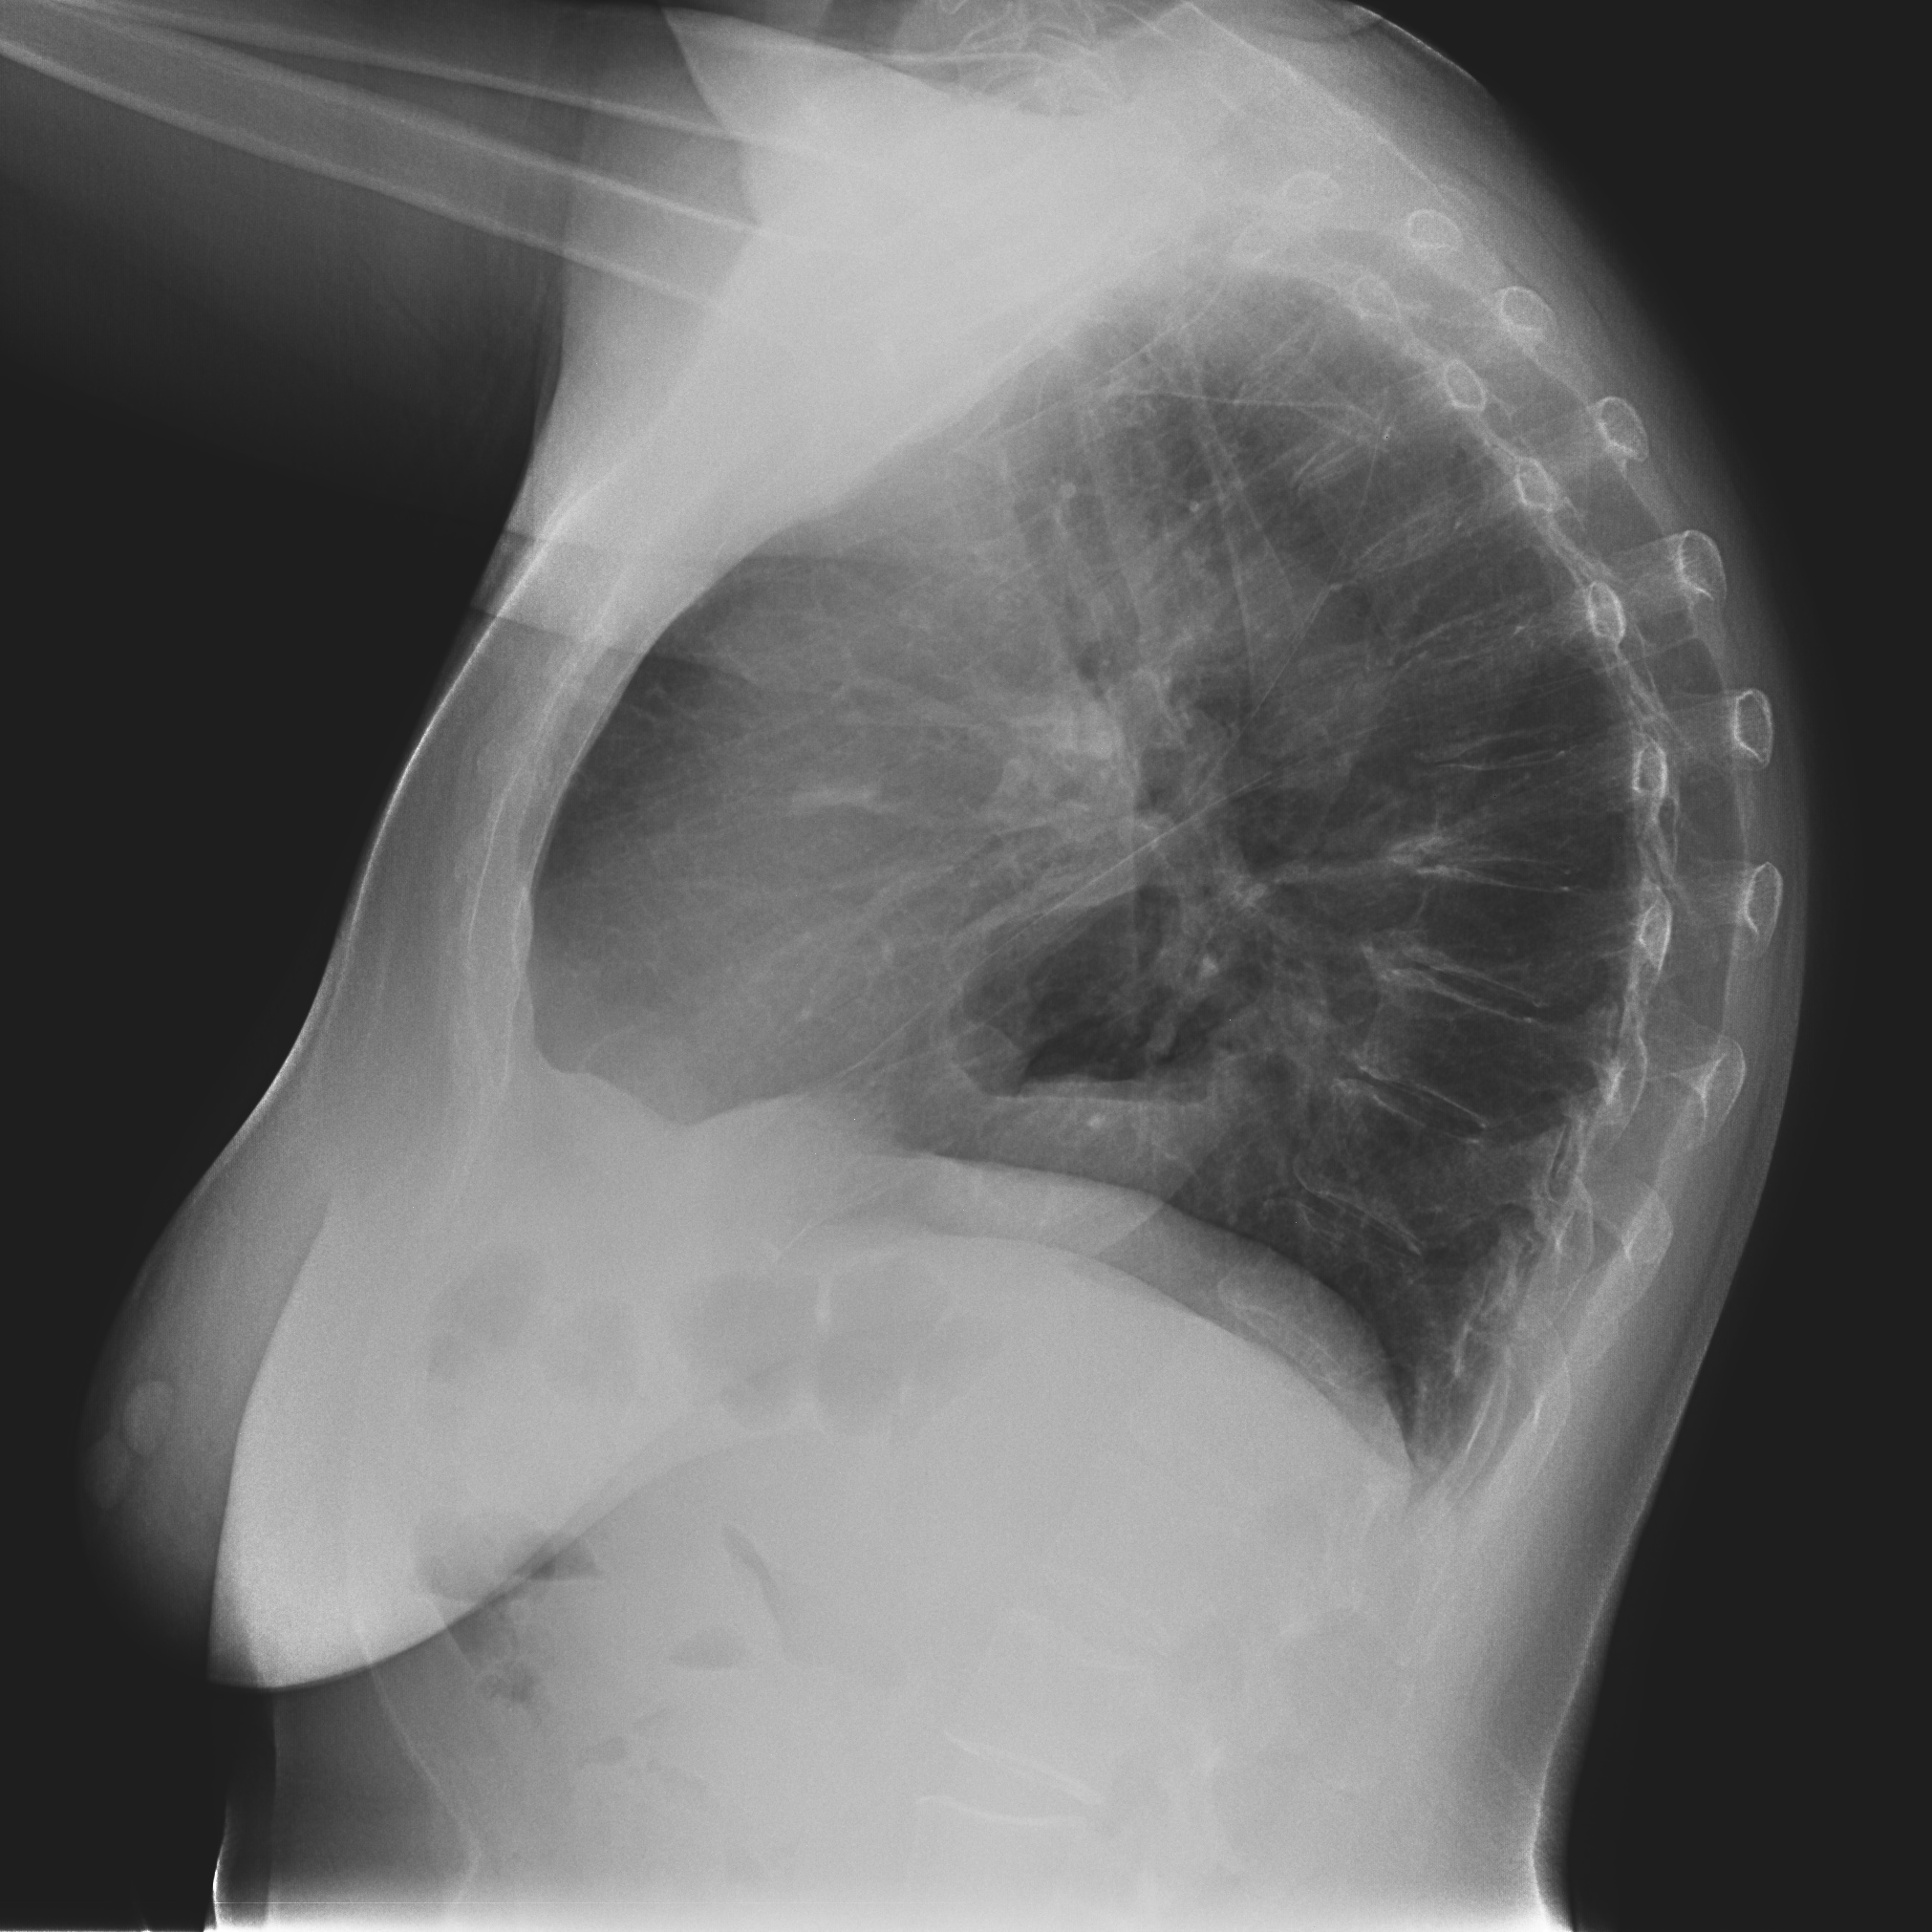

Nota: ¡¡¡No olvidar la placa lateral!!! La regla a seguir es la misma. Leer abdomen y diafragma, examinar parte posterior, tejidos blandos y subir por la columna; tráquea y descender por mediastino. Finalmente pulmones.

Solución: Es un estudio Normal. Silueta cardiomediastínica y parénquimas pulmonares sin alteraciones significativas.